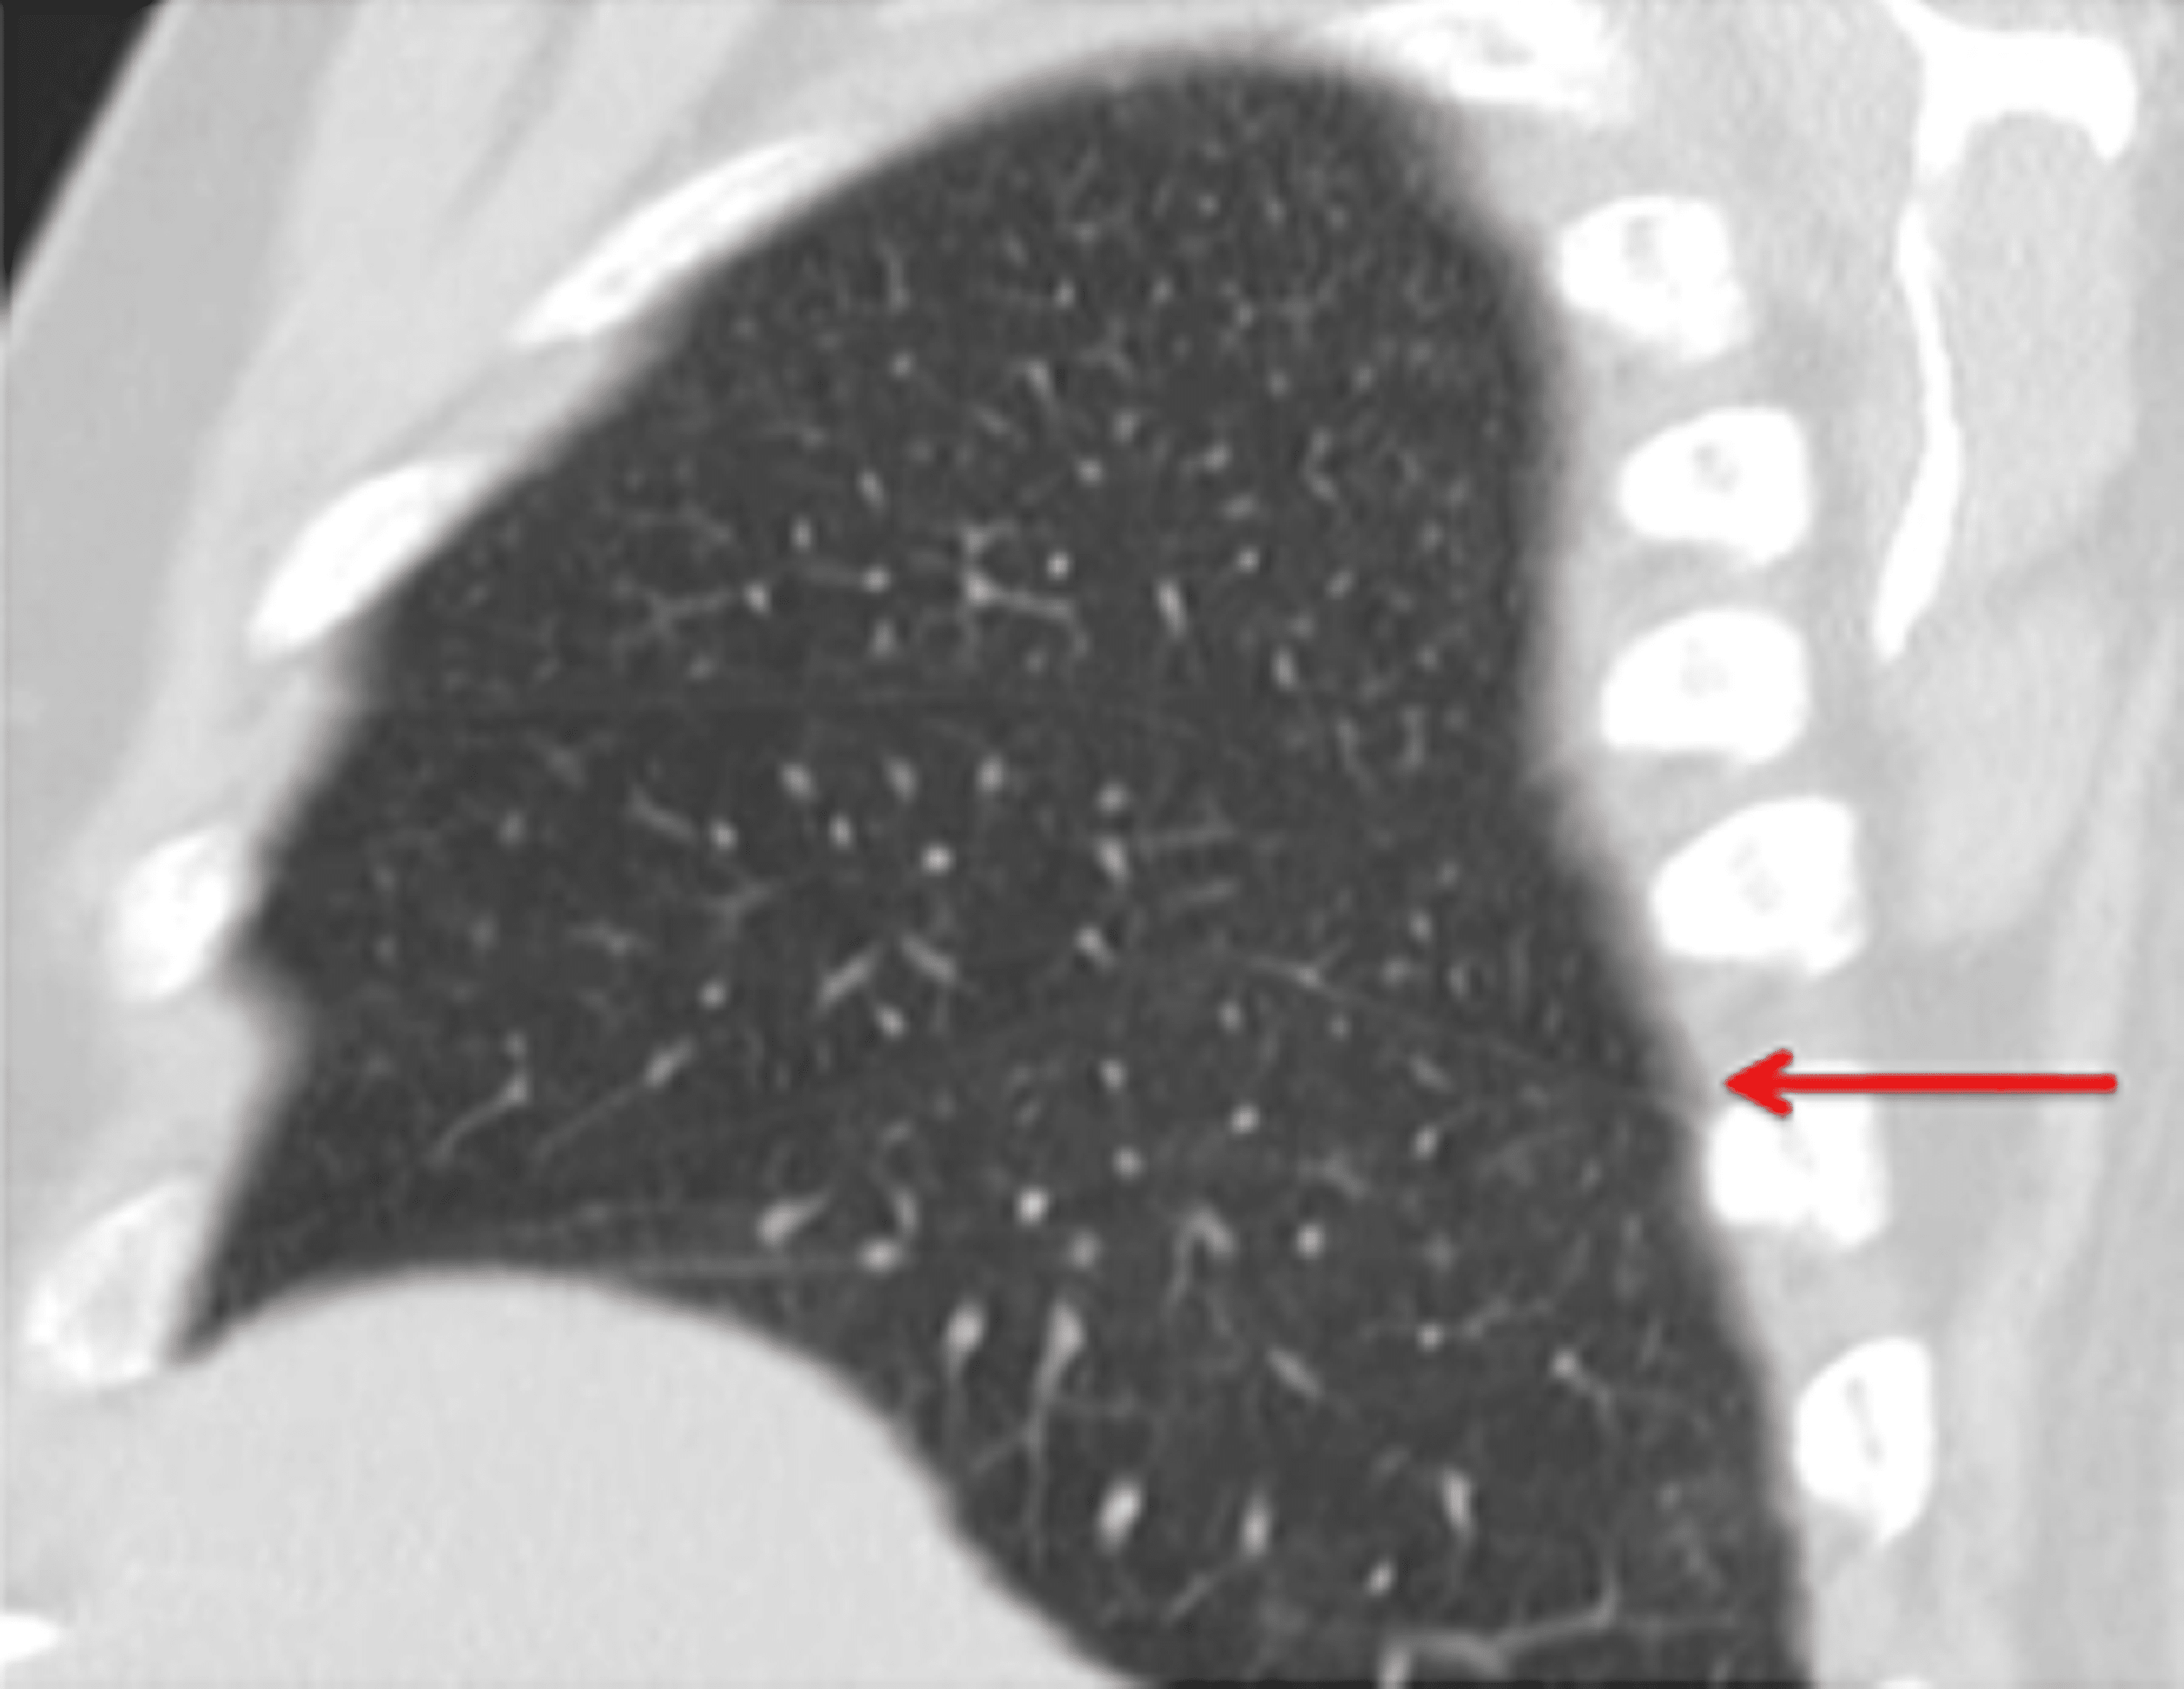

From radiopaedia.org

Right inferior accessory fissure Image Accessory Pulmonary Fissures Radiology Accessory and incomplete pulmonary fissures are often overlooked during routine imaging but can have profound clinical. Accessory fissures of the lung usually occur at the borders of bronchopulmonary segments. Each lung has an oblique fissure separating the upper lobes from the lower lobes and the right lung has a horizontal fissure that separates the right upper lobe from the middle.. Accessory Pulmonary Fissures Radiology.